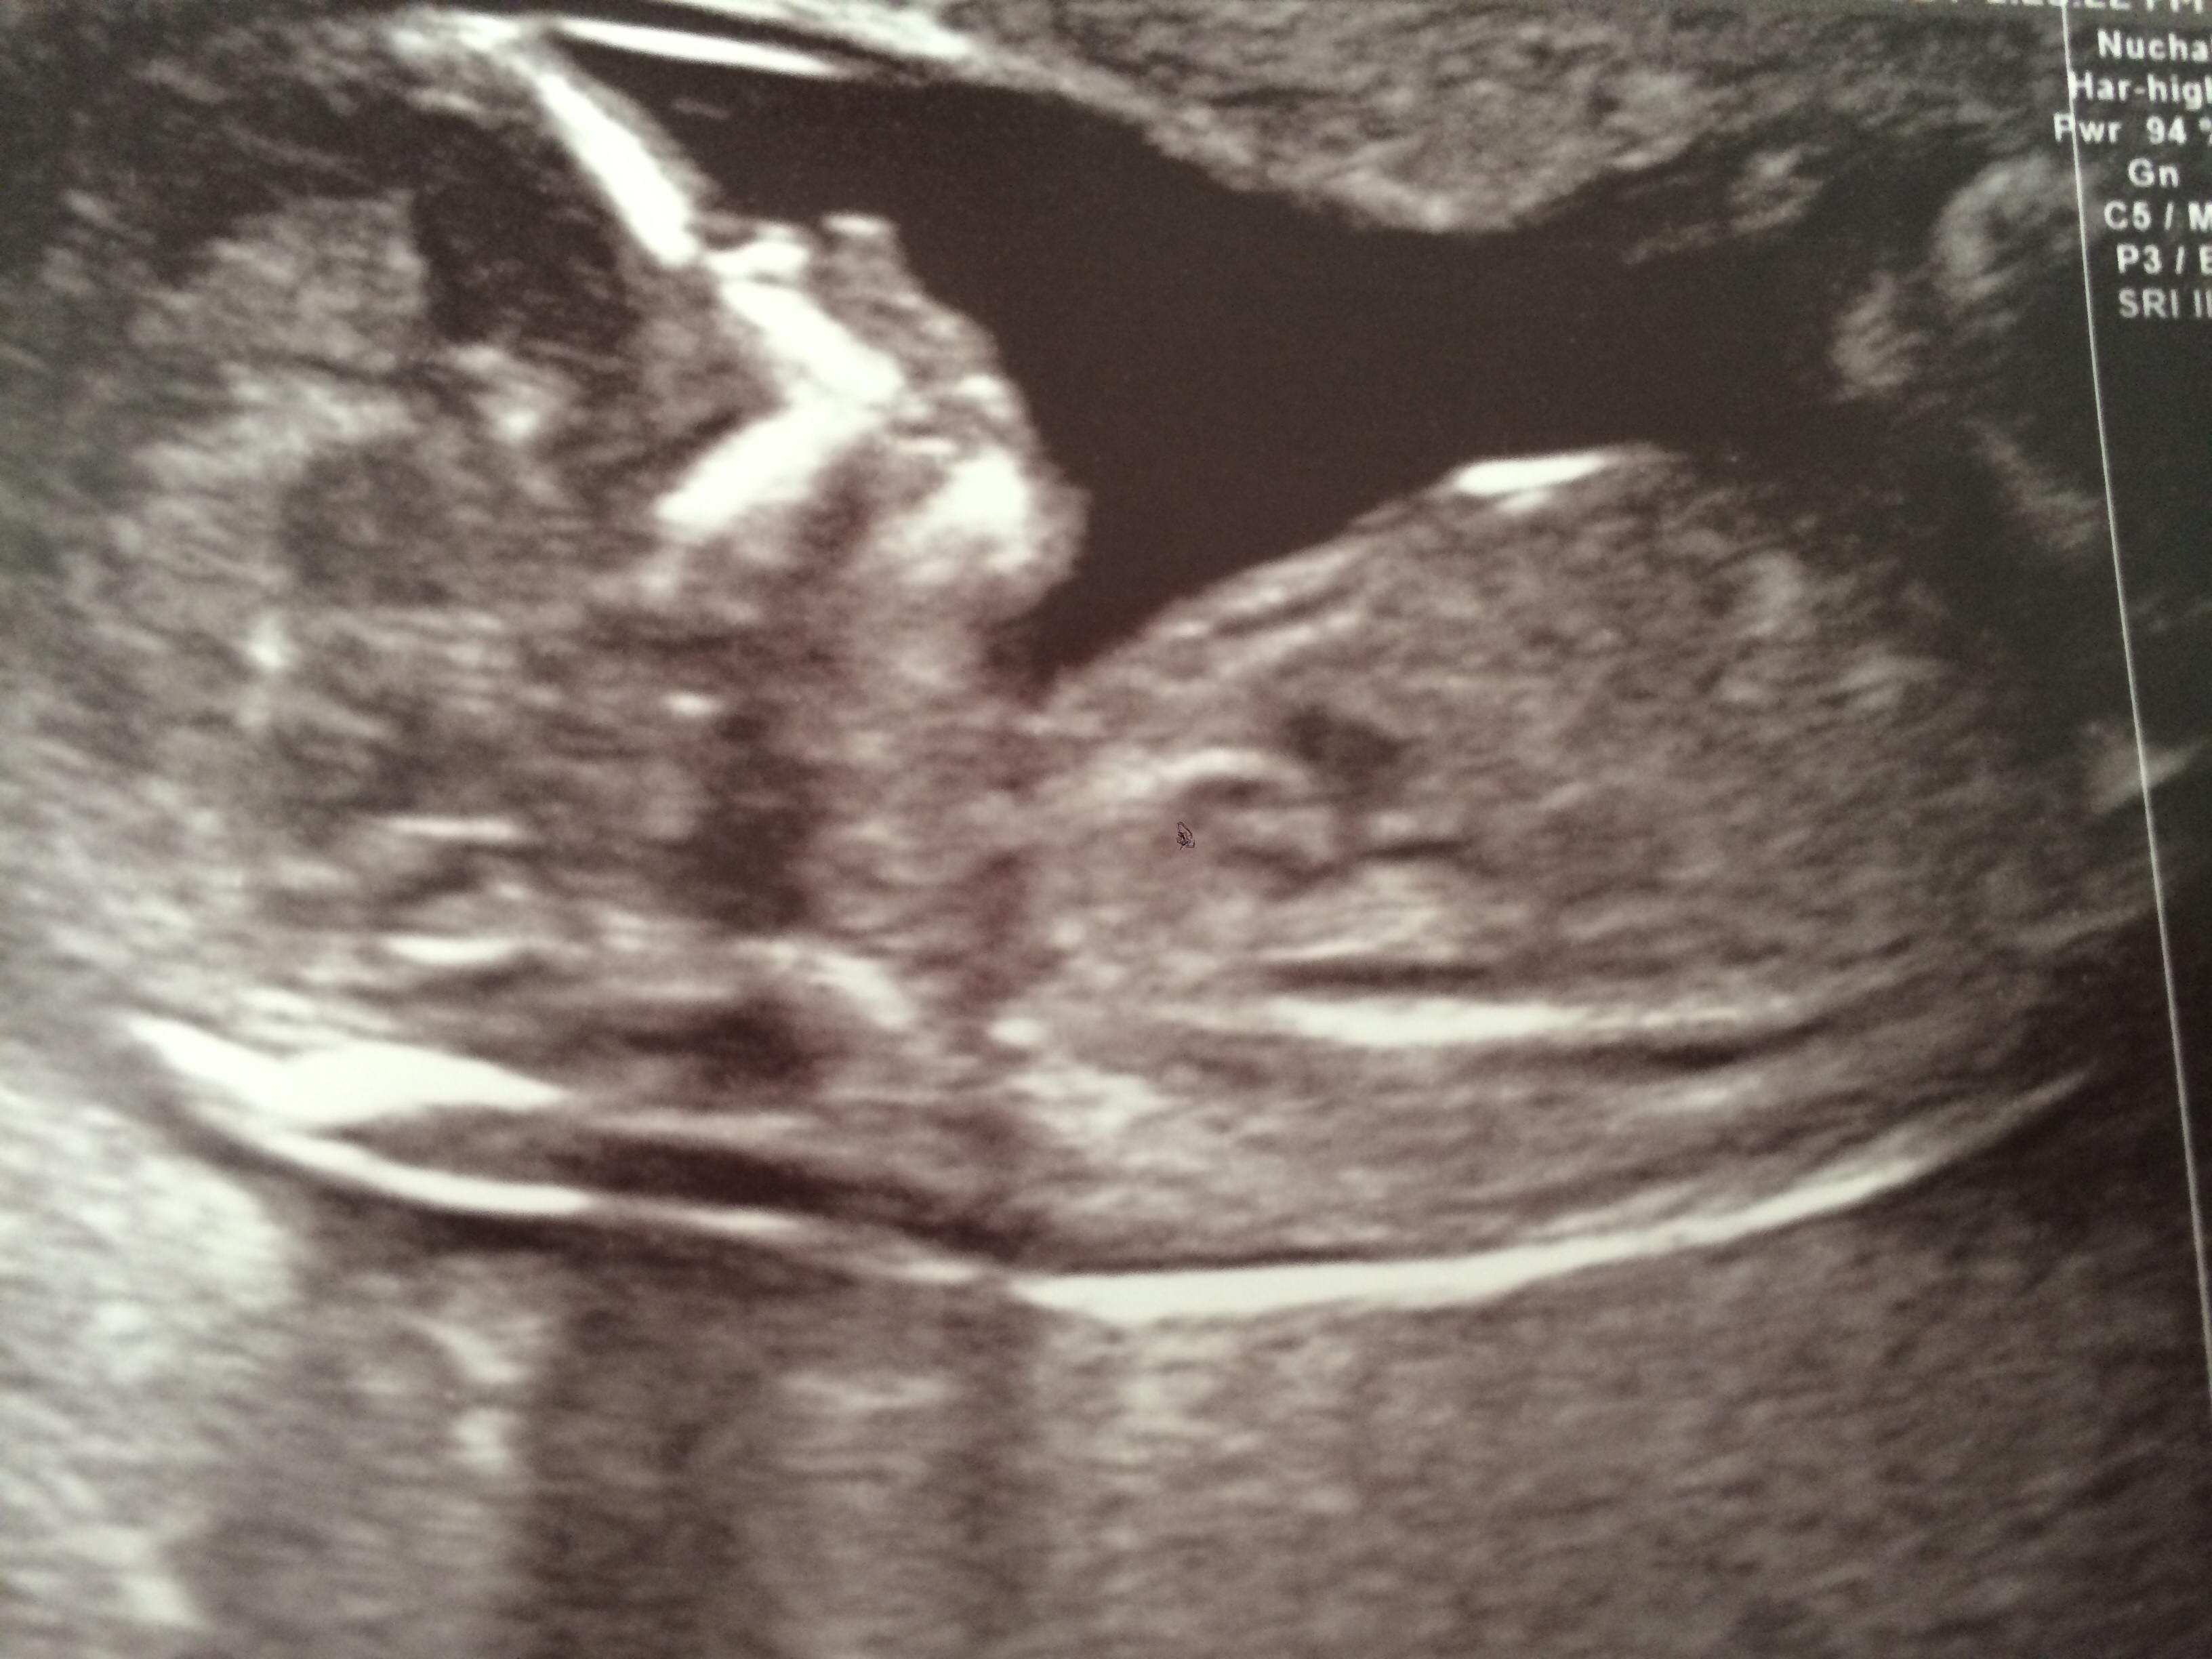

Been studying this picture so hard. At first I thought the white circle next to the baby's leg was the 'bits', but I'm pretty convinced now that it's cord, and a penis surely couldn't be that big at 13 weeks?!

I see 3 white lines at the bottom in between the legs, with the middle one slightly longer than the other two? but I'm not sure if I'm just seeing that because it's what I want to see. Any ideas? Would hugely appreciate it :)